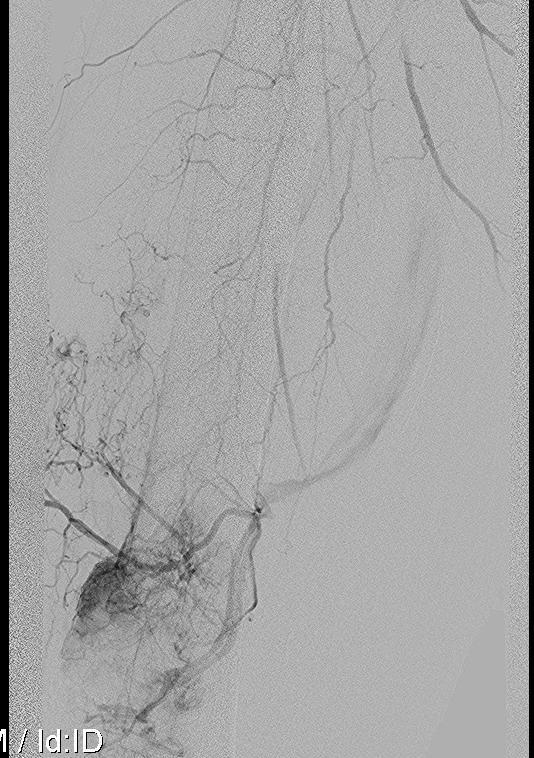

Subtrochanteric / Femoral shaft metastasis

Management

Reconstruction nail

- consider cement

- consider venting

Durability

- 217 patients treated with cephalomedullary nails for proximal femoral metastasis

- revision surgery required in 10%

- more common with survival > 7 months

Cement

- 43 patients with IMN + cement of femur and humerus versus 27 IMN

- lower pain scores with cement

- some reduction of metastasis progression with cement

Venting / Negative pressure reaming / Reamer Irrigator Aspirator

Risk of cardiopulmonary complications from fat / air / cancer emboli

- 73 femoral nails for metastatic impending fracture

- 2 deaths from fat embolism